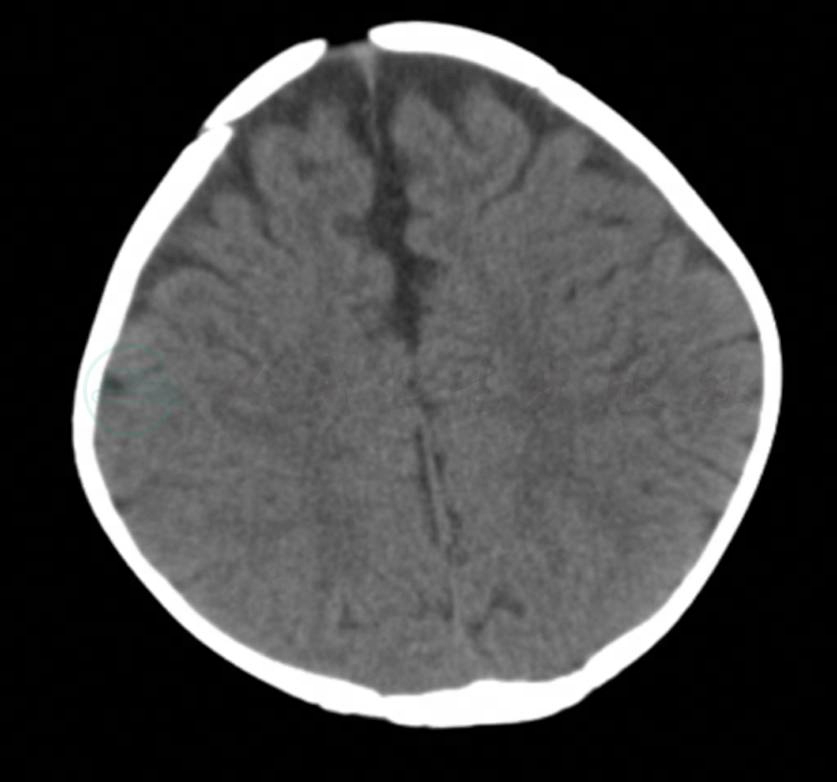

仅表现为颅骨缺损,无组织膨出,多数无症状,X线或CT检查可发现有颅骨缺损或颅缝闭合不全(图12-12-3)。

图12-12-3隐性颅裂CT表现

引自:临床疾病概要(第3版).第3版.ISBN:978-7-117-26065-7.主编: